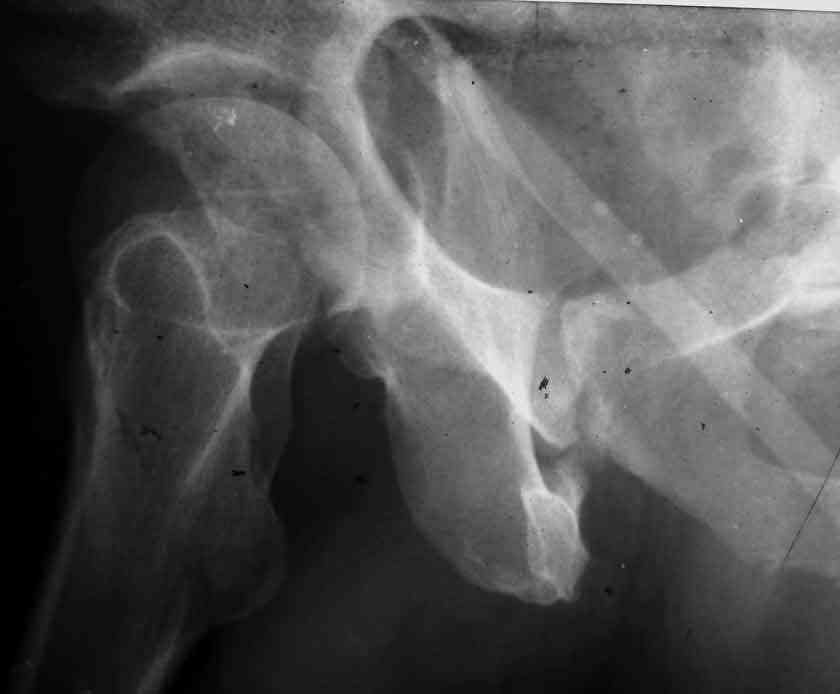

Dear Friends This is a 57 y old male.

Your input is welcome as to the classification of this fratcure, as well as the proposed management.

Unfortunately, CT is not available. Best Regards

Dear Sir it looks quite difficult classify this fracture because the iliac view is not so clear.

In my opinion it is a column fracture because the obturator foramen is interrupted. There is a fracture of the posterior wall. If we assume the ap view as an iliac view it could be an anterior comun fracture plus posterior wall. It is difficult also to judge the head of the femur.

Was the hip dislocated at the accident?

If you have not a CT scan I think that in order to have a good classification you should obtain a better view of the judet x rays.

From the x rays it appears like a bicolumnar fracture with iliac extension (AO C1).

CT scan is mandatory to evaluate such fractures more accurately and also to plan the treatment and surgery Most of the bicolumnar fractures of the high variety in experienced hands can be managed thro the ilioinguinal approach

I am sending another iliac view, and a marked version of the AP I already sent. In this AP, the

proximal part of the greater sciatic notch as well as the distal parts of the ilioischial and iliopubic lines are marked with a grey interrupted line. A white interrupted line marks what could be an exit through the obturator foramen, or so I assume.